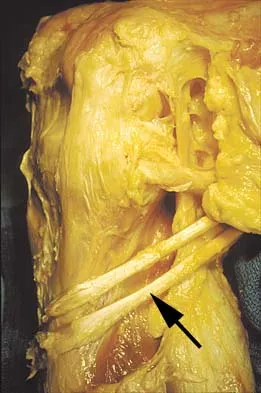

Figure 11 shows the anatomic dissection of the medial side of the knee joint after removal of the superficial fascia. The arrow is pointing to what structure?